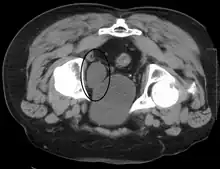

Investigations performed usually include collecting a sample of urine for an inspection for malignant cells under a microscope, called cytology, as well as medical imaging by a CT urogram or ultrasound.[29] If a concerning lesion is seen, a flexible camera may be inserted into the bladder, called cystoscopy, in order to view the lesion and take a biopsy, and a CT scan will be performed of other body parts (a CT scan of the chest, abdomen and pelvis) to look for additional metastatic lesions.[29]

Treatment depends on the cancer's stage. Cancer present only in the bladder may be removed surgically via cystoscopy; an injection of the chemotherapeutic mitomycin C may be performed at the same time.[29] Cancers that are high grade may be treated with an injection of the BCG vaccine into the bladder wall, and may require surgical removal if it does not resolve.[29] Cancer that is invading through the bladder wall may be managed by complete surgical removal of the bladder (radical cystectomy), with the ureters diverted into a segment of part of ileum connected to a stoma bag on the skin.[29] Prognosis can vary markedly depending on the cancer's stage and grade, with a better prognosis associated with tumours found only in the bladder, that are low grade, that do not invade through the bladder wall, and that is papillary in visual appearance.[29]

Some forms of medical imaging exist to visualise the bladder. A bladder ultrasound may be conducted to view how much urine is within the bladder, indicating urinary retention. A urinary tract ultrasound, conducted by a more trained operator, may be conducted to view whether there are stones, tumours or sites of obstruction within the bladder and urinary tract. A CT scan may also be ordered.